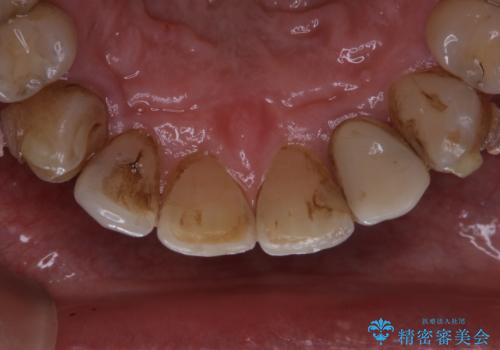

- インビザラインでの矯正中も、コーヒーを頻繁に飲むためステインが気になるとのことでした。PMTC60分コースでなんとかクリーニングを行いました。

インビザライン治療中には、歯の表面にアタッチメント(効率的に歯の移動をするもの)を設定します。そのため歯ブラシでは届きにくい細かい部分などに、歯石や着色がついてしまうことがあります。着色などを放置していると、着色なのか、虫歯なのかの判別もしずらく正確にお口の中の状態を診断できません。